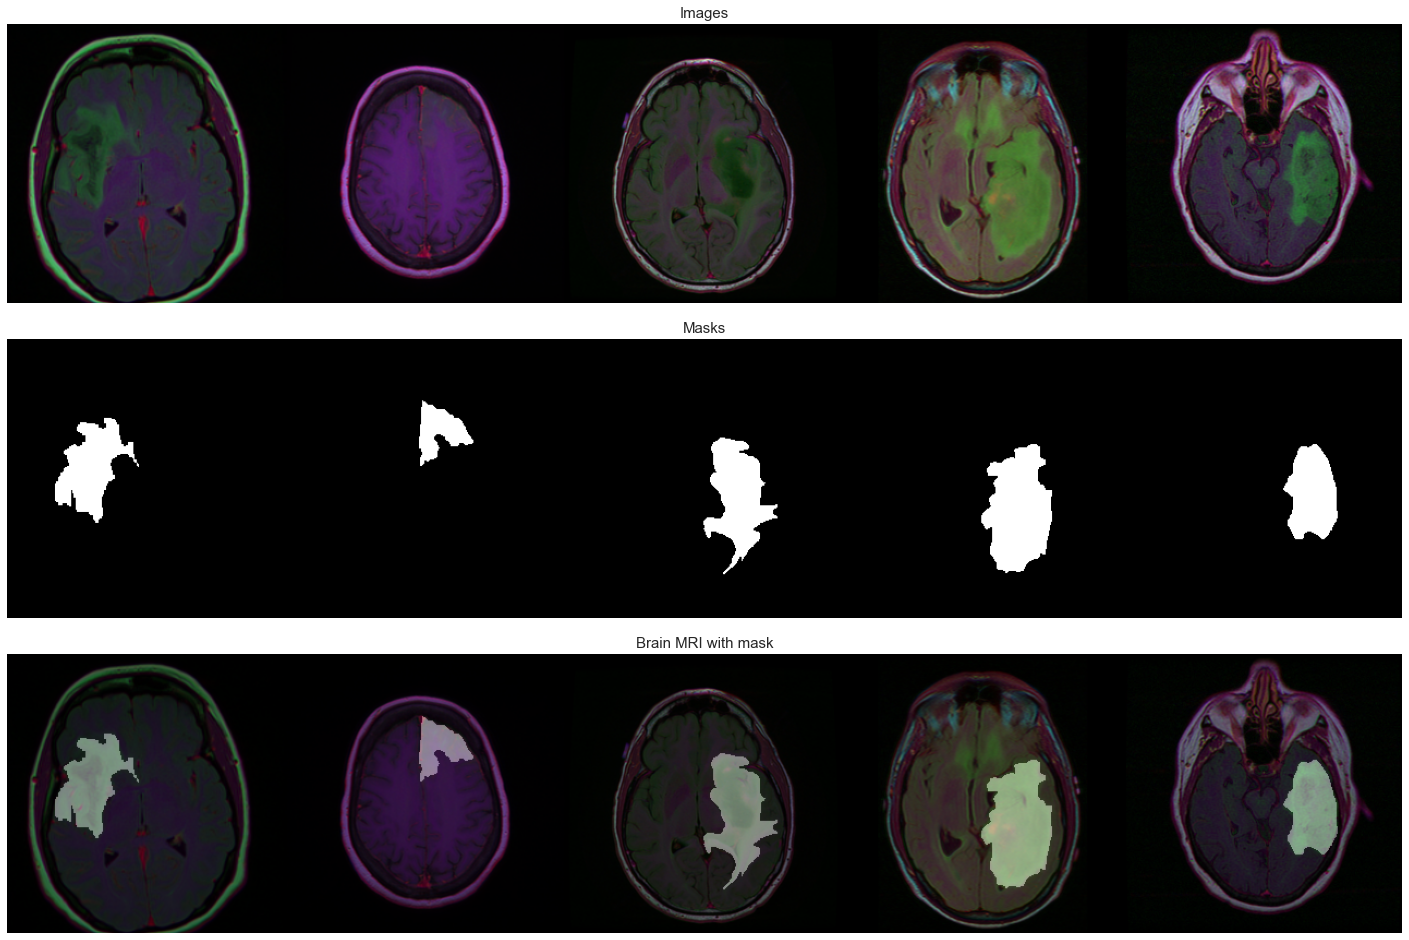

Computer Vision, OpenCV

I have significant research and practical experience in the field of computer vision. Moreover, I have used numerous computer vision techniques and libraries such as convolution filters, edge detectors, image segmentation, convolutional neural networks, YOLO, Attention Mechanism, Image captioning, Opencv and many others. Some of these applications are Facial Keypoint Detector, Image Captioning, Landmark Detection & Robot Tracking (SLAM), and many more.